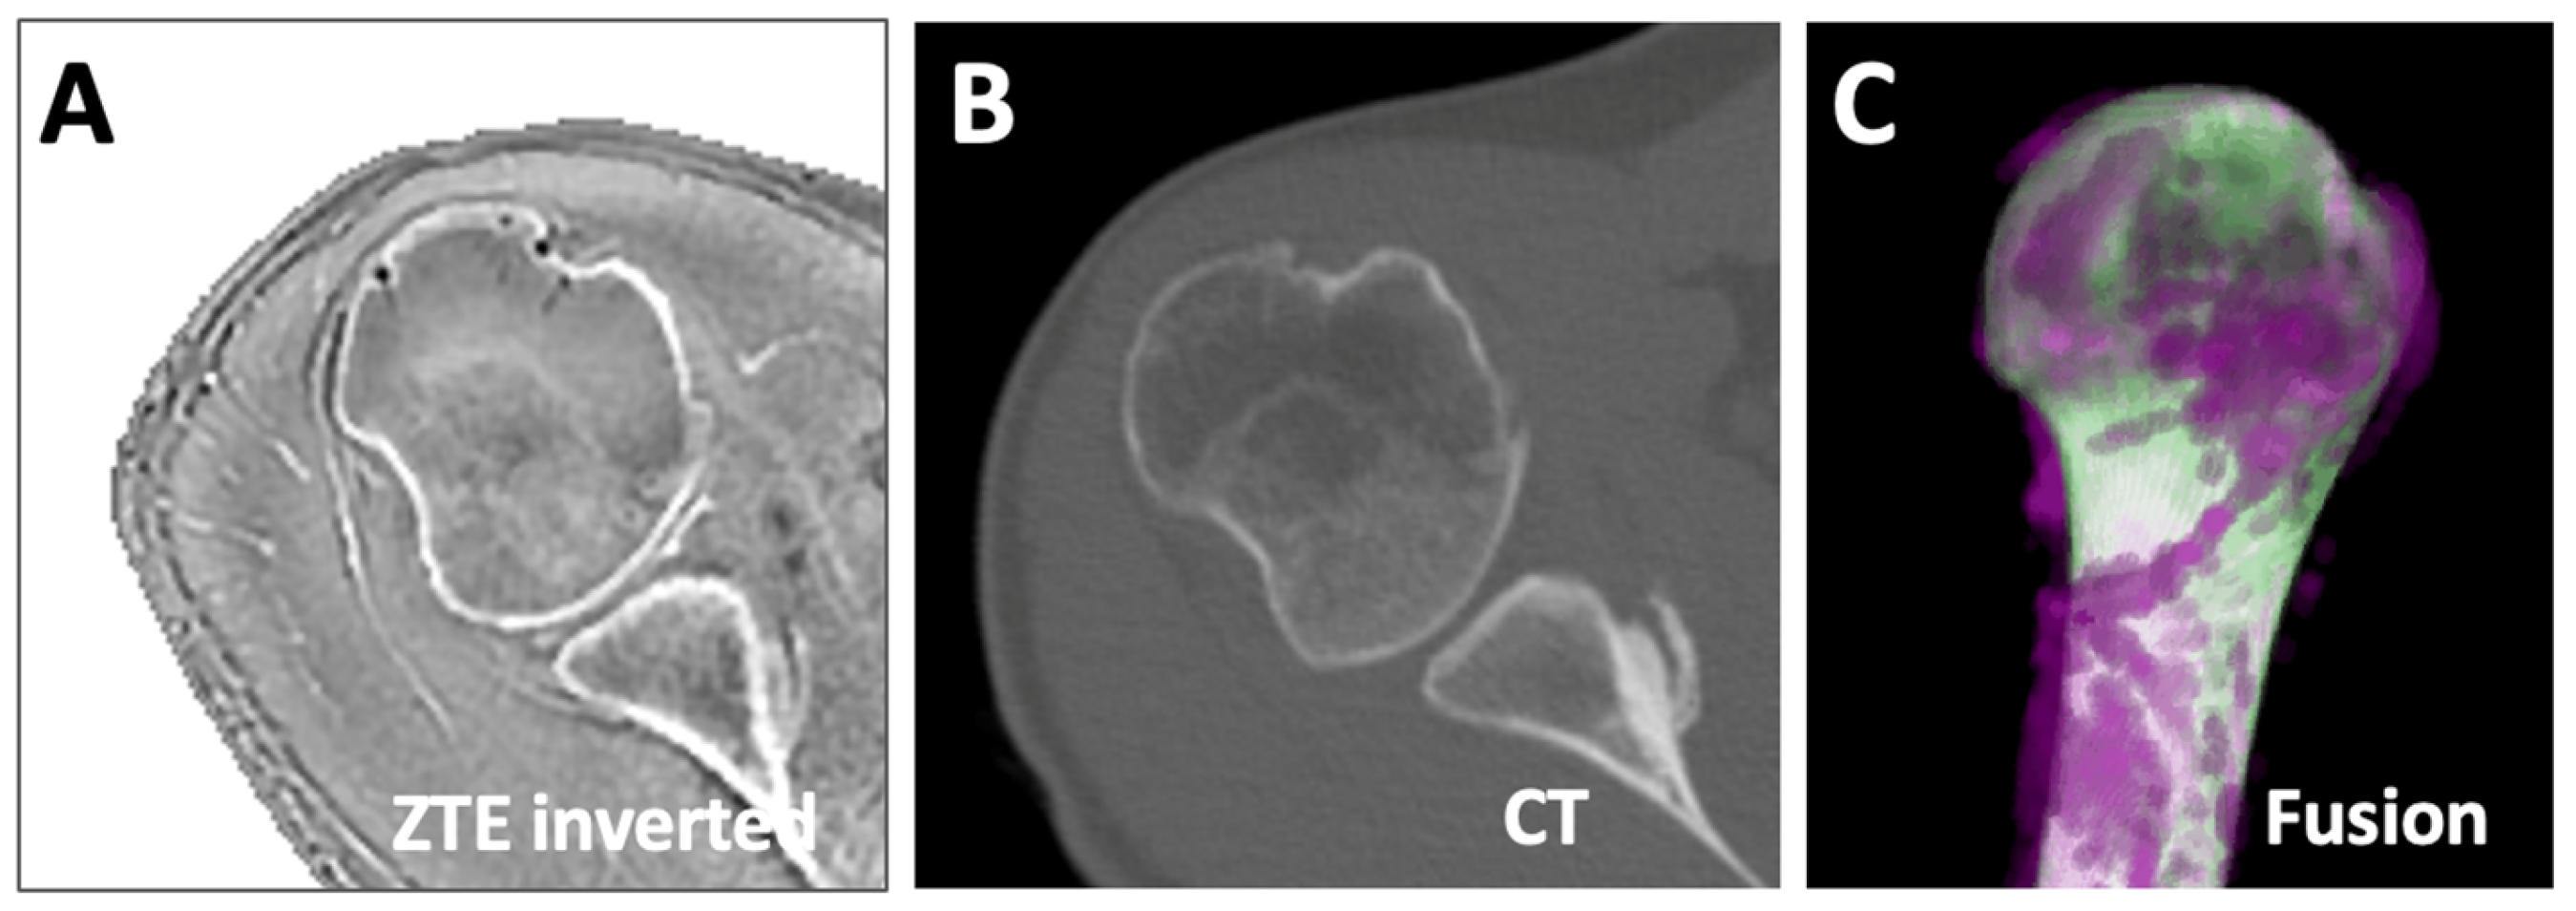

3.3. Comparison vs. CT

In the opportunistic data where both ZTE MRI (Figure 8A) and CT (Figure 8B) data were available from the same subject, the Dice score of the humerus segmentation using DL was 97%. We created a fused 3D rendering (Figure 8C), which shows an excellent overlap (white) between ZTE (purple) and CT (green), and is likely to yield similar values when measured for length, etc. However, this needs to be validated in additional samples.

Figure 8.

Comparison of MRI vs. CT segmentation. ZTE MRI (A) and CT (B) data of the same subject were registered and segmented (using U-Net for MRI, manually for CT). The segmented images were fused (C), showing the overlapping regions as white, and the non-overlapping regions in magenta for MRI and green for CT.